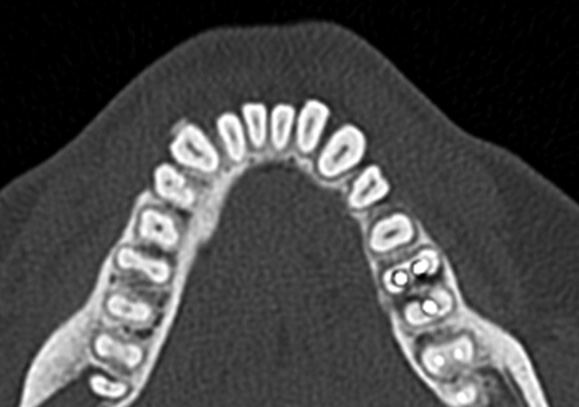

「断層撮影」は見たい部分を

輪切りにして画像化できるため、

見たい部分の厚みや深さ、

奥行きなどの情報を得ることも可能です。

1. 正確な位置がわかる

CTスキャンは3Dの画像のため、

埋まっている歯の正確な位置を把握できます。

これにより、歯がどの方向に埋まっているのか、

他の歯や骨との位置関係を

はっきりと知ることができます。

3. 安全に治療ができる

埋伏歯が神経や血管に近接している場合、

その位置関係を事前に把握することで、

手術中にそれらを傷つけないように

リスクを最小限に抑えることができます。